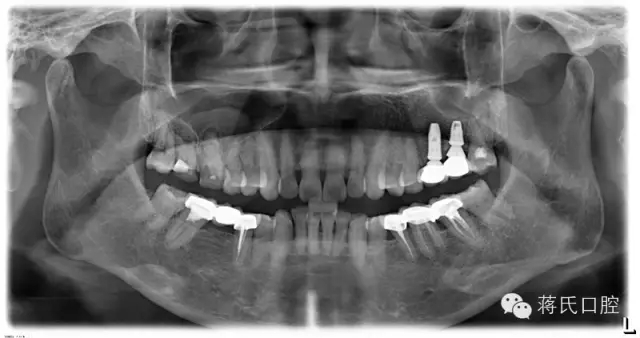

8.種植后全景片

12.修復(fù)后全景片